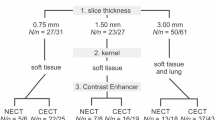

Study population, CT scans and their evaluation by radiologists

Multislice CT scans of the chest were obtained from 20 consecutive patients (mean age: 62.4 years; range: 29–84 years) at our center. All scans were performed using a 16-row MSCT unit (Sensation 16, Siemens Medical Solutions, Erlangen, Germany). The scan parameters used were tube voltage 120 kV, tube current 80 mAs at 0.5 s gantry revolution, 0.75-mm slice collimation and table feed of 19.2 mm/rot. Routinely, single phase peripheral intravenous power injection was performed using 80 ml nonionic contrast material of 300 mg/ml iodine concentration (Ultravist 300, Schering AG, Berlin, Germany) and subsequently 30 ml of normal saline solution at a flow of 2–3 ml/s. Image data were reconstructed using a lung filter kernel (B60f) at slice thickness settings of 4.0, 2.0 and 0.75 mm at 2.7-, 1.2- and 0.6-mm reconstruction increments (RI), respectively. The RST/RI settings were chosen to obtain image data comparable with standard single slice chest CT (RST = 4 mm; RI = 2.7 mm), standard chest MSCT with a limited numbers of resulting images (RST =2 mm; RI =1.2 mm) and MSCT with high isotropic resolution (RST =0.75 mm; RI =0.6 mm). Image data were stored and analyzed on a dedicated workstation not accessible for clinical routine. All CT image data were independently evaluated by two experienced chest radiologists who were blinded to the patient CT study and reconstruction protocol data. CT datasets were assessed using the interactive axial cine mode. Reader confidence for diagnosis of each pulmonary nodule was assessed and documented on a three-point scale (0= negative, 1= uncertain, 2= positive). The readers documented nodule position, diameter and solidity (solid, part solid and ground glass, as well as calcification). All image data were reevaluated by the two radiologists in consensus with the CAD results.

Standard of reference and nodule inclusion criteria

The reference standard was established by consensus of two independent experienced chest radiologists who evaluated all datasets (0.75-, 2.0-, 4.0-mm datasets, Fig. 2) in consensus with knowledge of the results of the study radiologists and CAD. The reference standard containing all nodules found on 0.75-mm slices was chosen for comparison of performance of CAD at different slice thicknesses. For comparison of CAD with reader performances for each of the reconstruction protocols, a portion of the reference standard containing all nodules detectable on each individual RST (4.0, 2.0 and 0.75 mm) was used as ground truth reference. Hereafter, results pertaining to the total number of nodules contained in the reference standard are referred to as absolute detection rates or absolute performances, and results pertaining to the reduced reference standard of nodules detectable in one particular RST setting are referred to as relative detection rates or relative performance. The nodule diameters were adapted in consensus from CAD measurement data or in cases of failed CAD detection revaluated manually or adapted from the study reader data. For assessment of the potential clinical significance of CAD performance in patients with incidental lung nodule findings, all nodules in our study were grouped according to a malignancy-probability and a resulting diameter-related clinical actionability equivalent (high actionability equivalent: nodule diameter ≥10.0 mm, intermediate actionability equivalent: nodule diameter of 4–9.9 mm and low actionability equivalent: nodule diameter <4 mm). Criteria for the diagnosis of a pulmonary nodule were the presence of a well-demarcated, solid, part-solid or ground glass spherical to irregular structure that, if solid, should have a density in the range of soft tissue or above or otherwise be well above the surrounding lung parenchyma (Fig. 2). Linear and subpleural densities that were attributable to pleural adhesions without nodular aspect were excluded from the reference standard. Bronchial wall thickening, thickening of interlobular septa and linear or reticular interstitial changes were excluded, as were areas of air space consolidation and regions with movement artifacts that would not allow for safe differentiation between pulmonary nodules and bronchial or vascular structures.